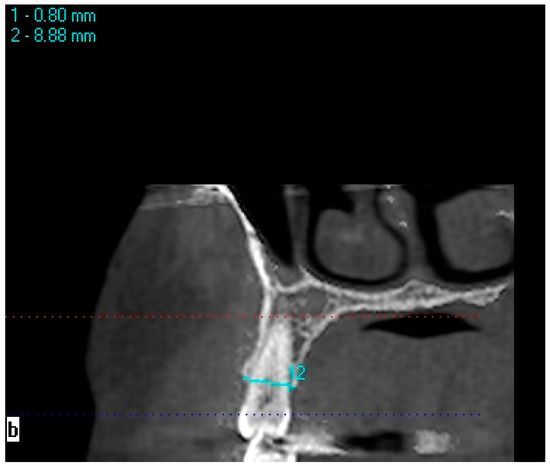

Bone measurements in areas with one missing tooth were made on 1.2 mm thick cross-sectional CBCT images obtained using the KaVo eXamVision (KaVo Dental GmbH, Biberach, Germany) program. Bone width was measured at the midpoint of the mesiodistal width of the edentulous region, 0.8 mm below the ridge crest, on the line connecting the vestibule/palatal and buccal/lingual walls (Figure 1). Bone width measurements at 2.8, 4.8, and 6.8 mm depths were performed following the same protocol as the bone width measurements performed at a 0.8 mm depth. The horizontal and vertical lines at 0.8 mm were used as the reference for the calculation of the depths. The protocol for edentulous crest measurements was applied in the same way for symmetrical toothed side measurements. Bone width measurements of symmetrical teeth were made with reference to the line that passes 0.8 mm below the lower crest of one of the buccal/vestibule and lingual/palatal bone walls (Figure 2). Bone heights were obtained through linear measurement of the distance between the reference point at the crest (the midpoint of the line at which bone width measurements were made) and the mandibular canal, maxillary sinus, mental foramen, and nasal floor. Intra-examiner reliability was calculated to assess the reliability of the measurements. The measurements in this study were performed by a single investigator specializing in oral and maxillofacial radiology. The second measurements were performed 4 weeks after the first measurement.

Figure 2. Measurement of bone width in the right second premolar area.